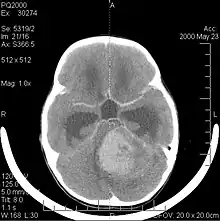

La tomodensitométrie (TDM) et L'imagerie par résonance magnétique (IRM) peuvent détecter efficacement une néoplasie dans le cerveau. L'IRM est plus sensible que la TDM pour identifier les lésions, mais présente des contre- indications pour les patients porteurs de stimulateurs cardiaques, de prothèses incompatibles, de clips métalliques et contre-indications. La TDM reste la méthode de choix pour détecter les calcifications au sein des lésions ou les érosions osseuses de la calotte ou de base du crâne. L'utilisation d' agents de contraste, iodés dans le cas du scanner et paramagnétiques (gadolinium) dans le cas de l'IRM, permet l'acquisition d'informations sur la vascularisation et l'intégrité de la barrière hémato-encéphalique, une meilleure définition de la tumeur tumorale par rapport à l' œdème environnant et à la génération d' hypothèses sur le degré de malignité. L'examen radiologique permet également d'évaluer les effets mécaniques et les modifications importantes des structures cérébrales résultant de la tumeur, telles que l' hydrocéphalie et les hernies, dont les effets peuvent être fatals. Enfin, en préparation à la chirurgie, ce diagnostic peut être utilisé pour déterminer la localisation de la lésion ou l'infiltration de la tumeur dans des zones vitales du cerveau. À cette fin, l'IRM est plus efficace que la tomodensitométrie car elle peut fournir des images en trois dimensions.

Les outils d'imagerie radiologique diagnostique mettent en évidence la modification du tissu néoplasique par rapport au parenchyme cérébral normal (par le biais de modifications de la densité tissulaire imagée électroniquement en TDM et de l'intensité du signal en IRM). Comme la plupart des tissus pathologiques, les tumeurs sont également reconnaissables par une accumulation accrue d'eau intracellulaire. Dans la tomodensitométrie, ils apparaissent hypodenses, c'est-à-dire de moindre densité que le parenchyme cérébral, dans la tomographie par résonance magnétique nucléaire avec relaxation spin-réseau hypointense et en relaxation spin-spin ainsi que l' hypersignal en pondération protonique (PD).

La tomodensitométrie du cerveau montre généralement une masse tissulaire qui peut être améliorée par l'un ou l'autre contraste. Au scanner, les gliomes de bas grade apparaissent généralement isodenses au parenchyme normal et peuvent donc ne pas présenter de rehaussement de contraste. De même, les lésions de la fosse crânienne postérieure sont difficiles à identifier au scanner. Par conséquent, les seuls résultats d'une telle tomographie ne sont pas toujours suffisants à des fins diagnostiques. Dans les cas douteux, l'utilisation de l'imagerie par résonance magnétique plus sensible est indispensable.

Sur-L'IRM montre une tumeur intracrânienne comme une lésion massive qui peut devenir plus luminescente après utilisation du produit de contraste. Cependant, il y a toujours une anomalie de signal dans -L'imagerie par résonance magnétique, qui indique la présence d'une néoplasie ou d'un œdème vasogénique. Habituellement, une luminescence accrue (amélioration du contraste) indique une tumeur d'un grade supérieur de malignité. Un anneau de contraste est caractéristique du glioblastome, avec la partie luminescente correspondant à la partie vitale de la tumeur maligne, et la plus foncée - zone hypointense correspondant à une nécrose tissulaire.

Les tumeurs des cellules gliales les plus courantes et les plus malignes sont les glioblastomes. Ils consistent en une masse hétérogène de cellules d'astrocytome peu différenciées principalement chez l'adulte. Ils surviennent généralement dans les hémisphères cérébraux, plus rarement dans le tronc cérébral ou la moelle épinière. Sauf dans de très rares cas, comme toutes les tumeurs cérébrales, elles ne s'étendent pas au-delà des structures du système nerveux central.

Le glioblastome peut provenir d'une forme diffuse (II. grade) ou un astrocytome anaplasique (III. grade) développer. Dans ce dernier cas, il est dit secondaire. Cependant, lorsqu'elle survient sans antécédent ni signe de malignité antérieure, on parle de maladie primaire. Les glioblastomes sont traités par chirurgie, radiothérapie et chimiothérapie. Ils sont difficiles à guérir et rares sont les cas qui survivent au-delà de trois ans.